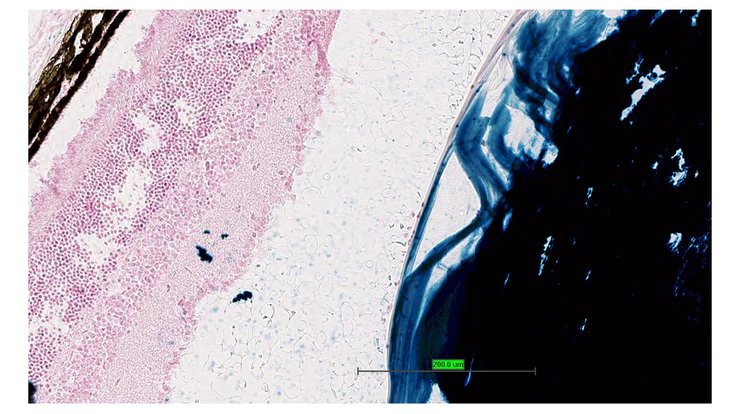

TS28: eye Present UC Davis_1888857

TS28: eye Present UC Davis_1888858

TS28: eye Present UC Davis_1888859